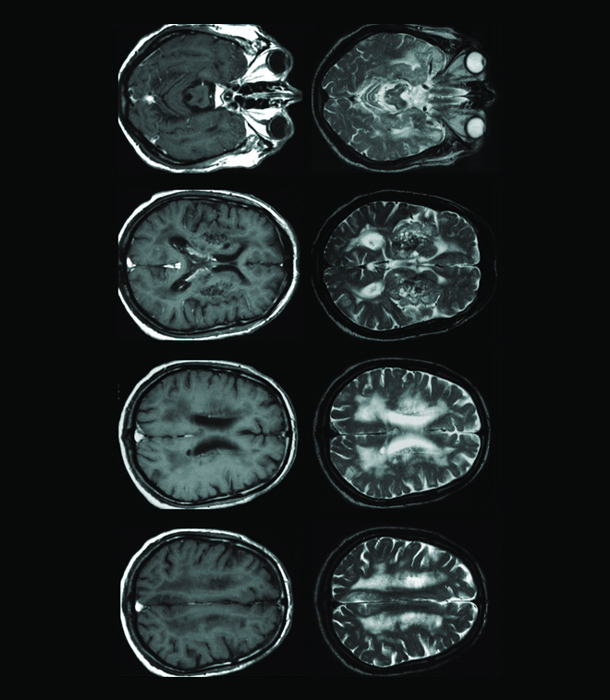

CEREBROVA CULAR DISEASE

This treatment method aims to encourage repair of damaged blood vessels and generation of new blood vessels by administering stem cells and to improve symptoms of cerebrovascular disease by restoring blood flow and suppressing inflammation.